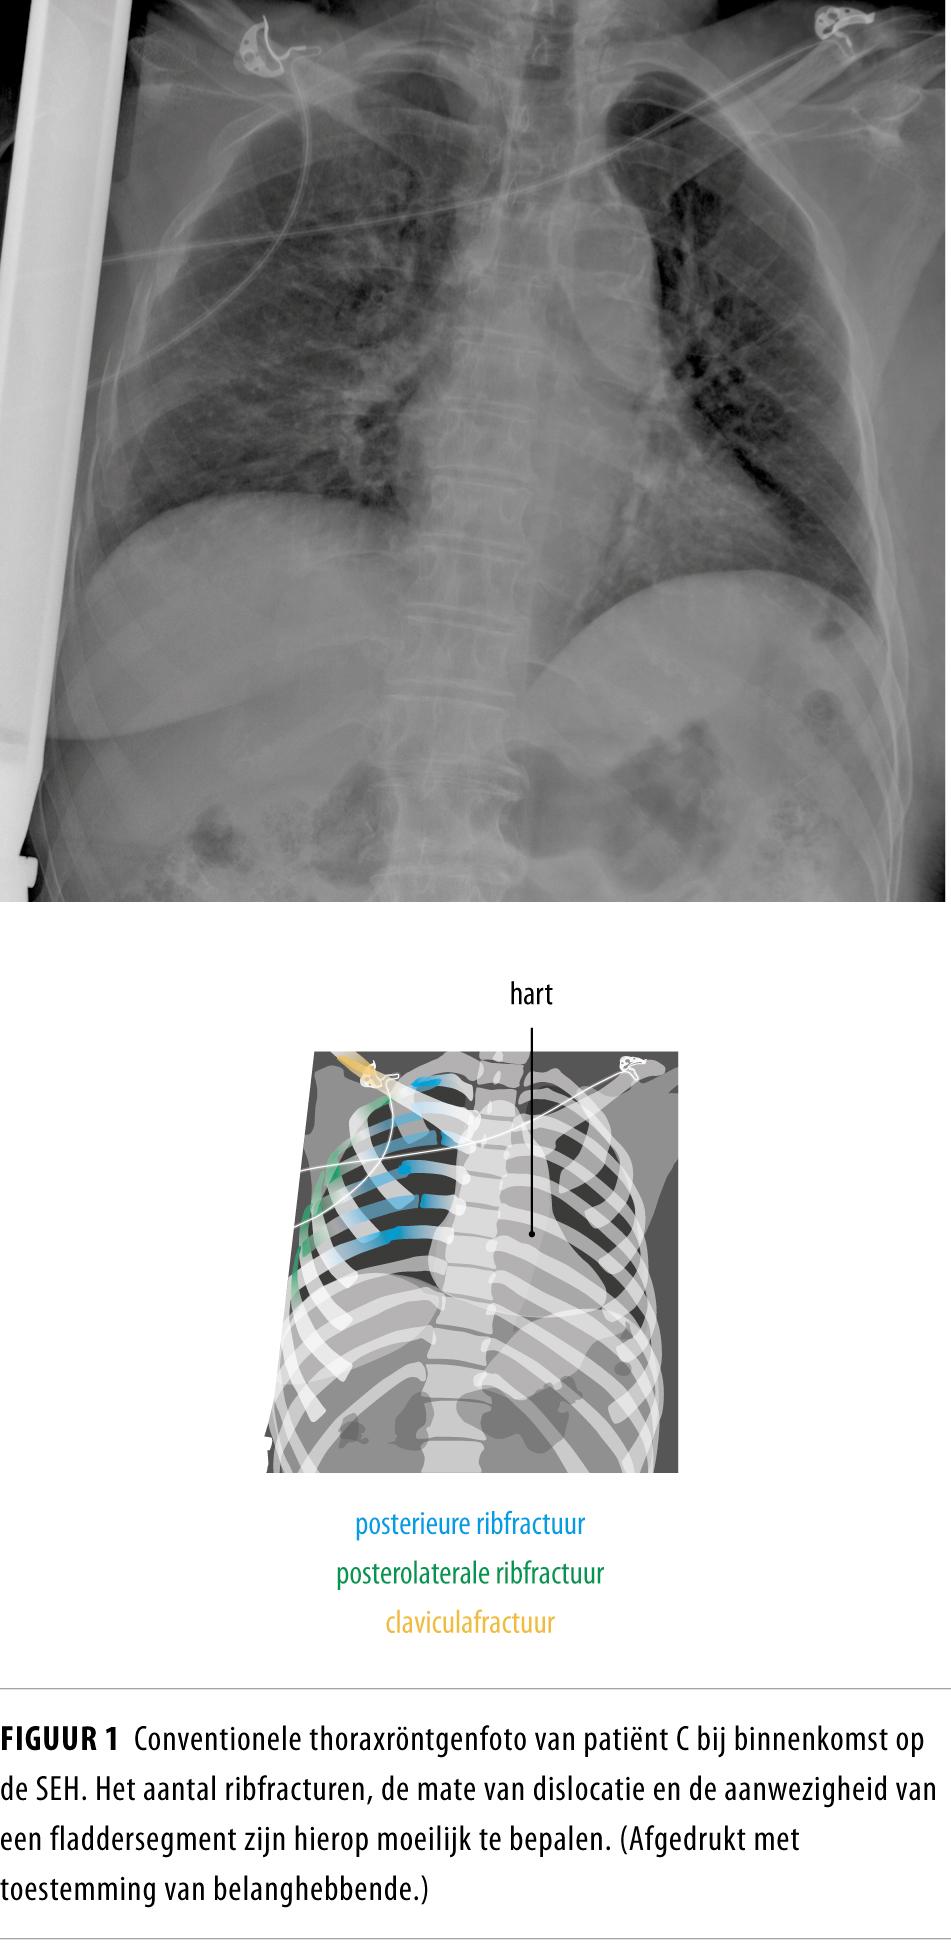

Bij opvang op de SEH had patiënte een versnelde en pijnlijke ademhaling (ademfrequentie: 26/min). De zuurstofsaturatie was goed met zuurstof via een beademingsmasker (12 l/min). De rechter hemithorax was pijnlijk en vertoonde een paradoxale ademhaling. Op een conventionele röntgenfoto waren multipele ribfracturen aan de rechter zijde te zien (figuur 1). Een CT-thorax toonde fracturen van ribben 2-11 rechts, waarbij ribben 4-8 op 2 plaatsen waren gebroken (figuur 2). Er was ook een kleine randpneumothorax. Verdere traumascreening toonde een claviculafractuur rechts, een ramus inferior- en superiorfractuur van het os pubis beiderzijds en een enkelfractuur rechts.

Diagnostische factoren Het is van essentieel belang om een oudere patiënt met stomp thoraxletsel goed in kaart te brengen om zo een gedegen risico-inschatting te maken. Omdat de ernst van het letsel met een conventionele thoraxröntgenfoto vaak wordt onderschat, adviseren wij om zeker bij een oudere patiënt met aanwijzingen voor ribfracturen laagdrempelig een CT-scan van de thorax te vervaardigen.4 Hiermee kan nauwkeurig het aantal ribfracturen, een longcontusie, een hemato- of pneumothorax, atelectase of bijkomende andere letsels worden gediagnosticeerd, of een fladderthorax worden aangetoond.